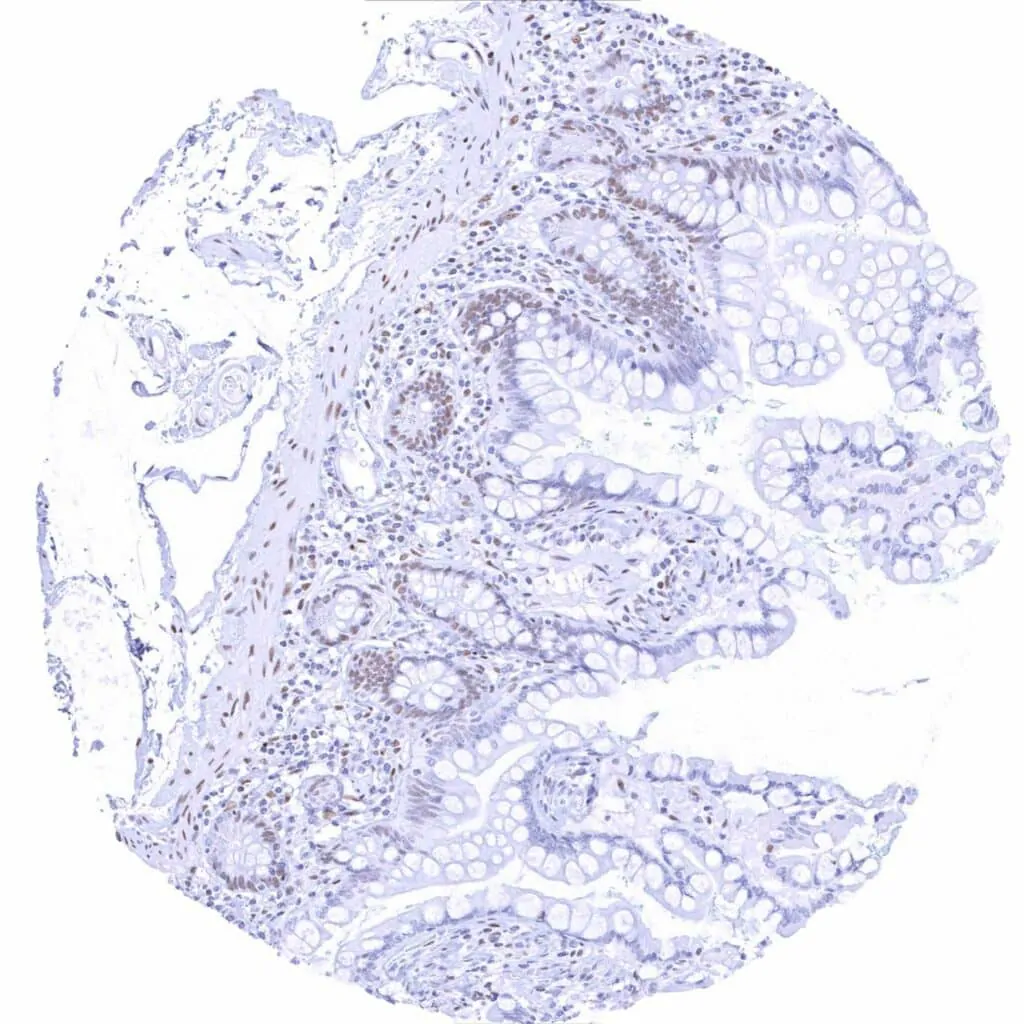

Rectum, mucosa – Weak to moderate TLE1 staining in epithelial cells. Staining is stronger in crypts than at the surface